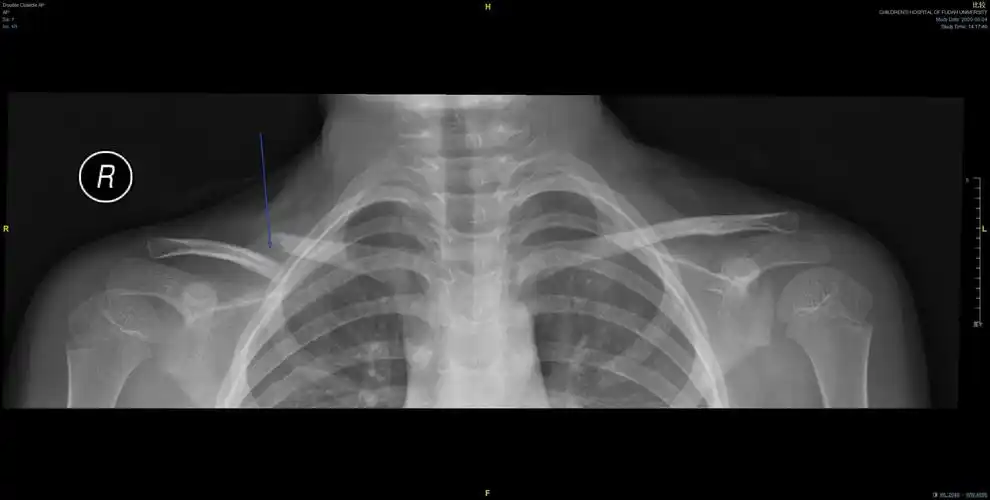

儿童锁骨骨折手术治疗(大于12岁)

儿童锁骨骨折保守治疗12岁以下

x射线的左锁骨儿童锁骨骨折骨折合并标记积极负面

dr片显示:左锁骨远端骨折